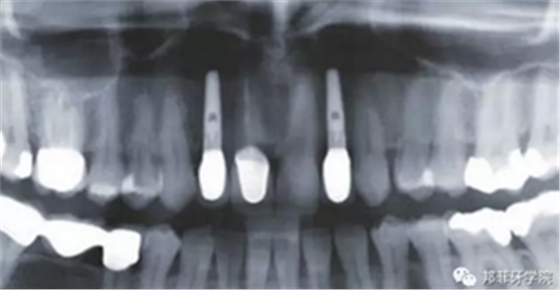

26歲女性患者,雙側上頜側切牙先天缺失,對原有修復體的“形態(tài)”、“光澤”等方面不滿意,希望重新修復(圖1&2)。12及22原為粘接橋修復,11根管治療史;拆除原修復體后余鄰牙完整,未見病理性探診深度。無系統(tǒng)疾病史?;颊咂谕递^高,告知治療流程佩戴臨時卡環(huán)義齒等(圖3)、費用、風險后表示接受治療。

圖2:治療前全景片